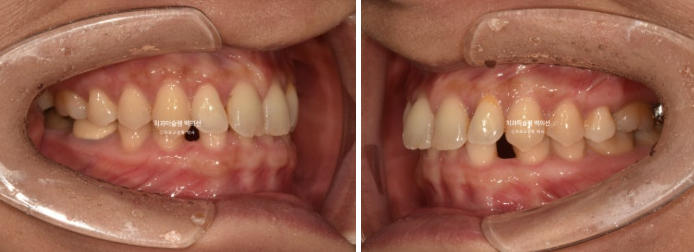

24.08~25.08

쓰러져 있던 두번째 큰어금니는 잘 세웠습니다.

1년에 걸쳐 교정치료기간 동안 아래 앞니공간이 이동하는 모습은 이러합니다.